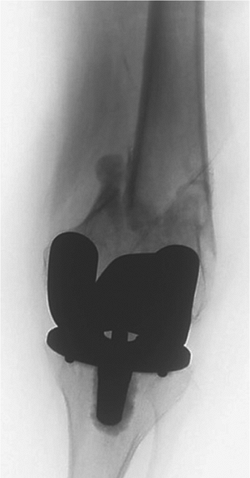

![]() |

|

Figure 45.12.

Injury AP film of a periprosthetic tibial-shaft fracture below a stable implant. The fracture was considered displaced and unstable. |

Figure 45.13. Postoperative AP film depicting plate and screw osteosynthesis of the fracture.